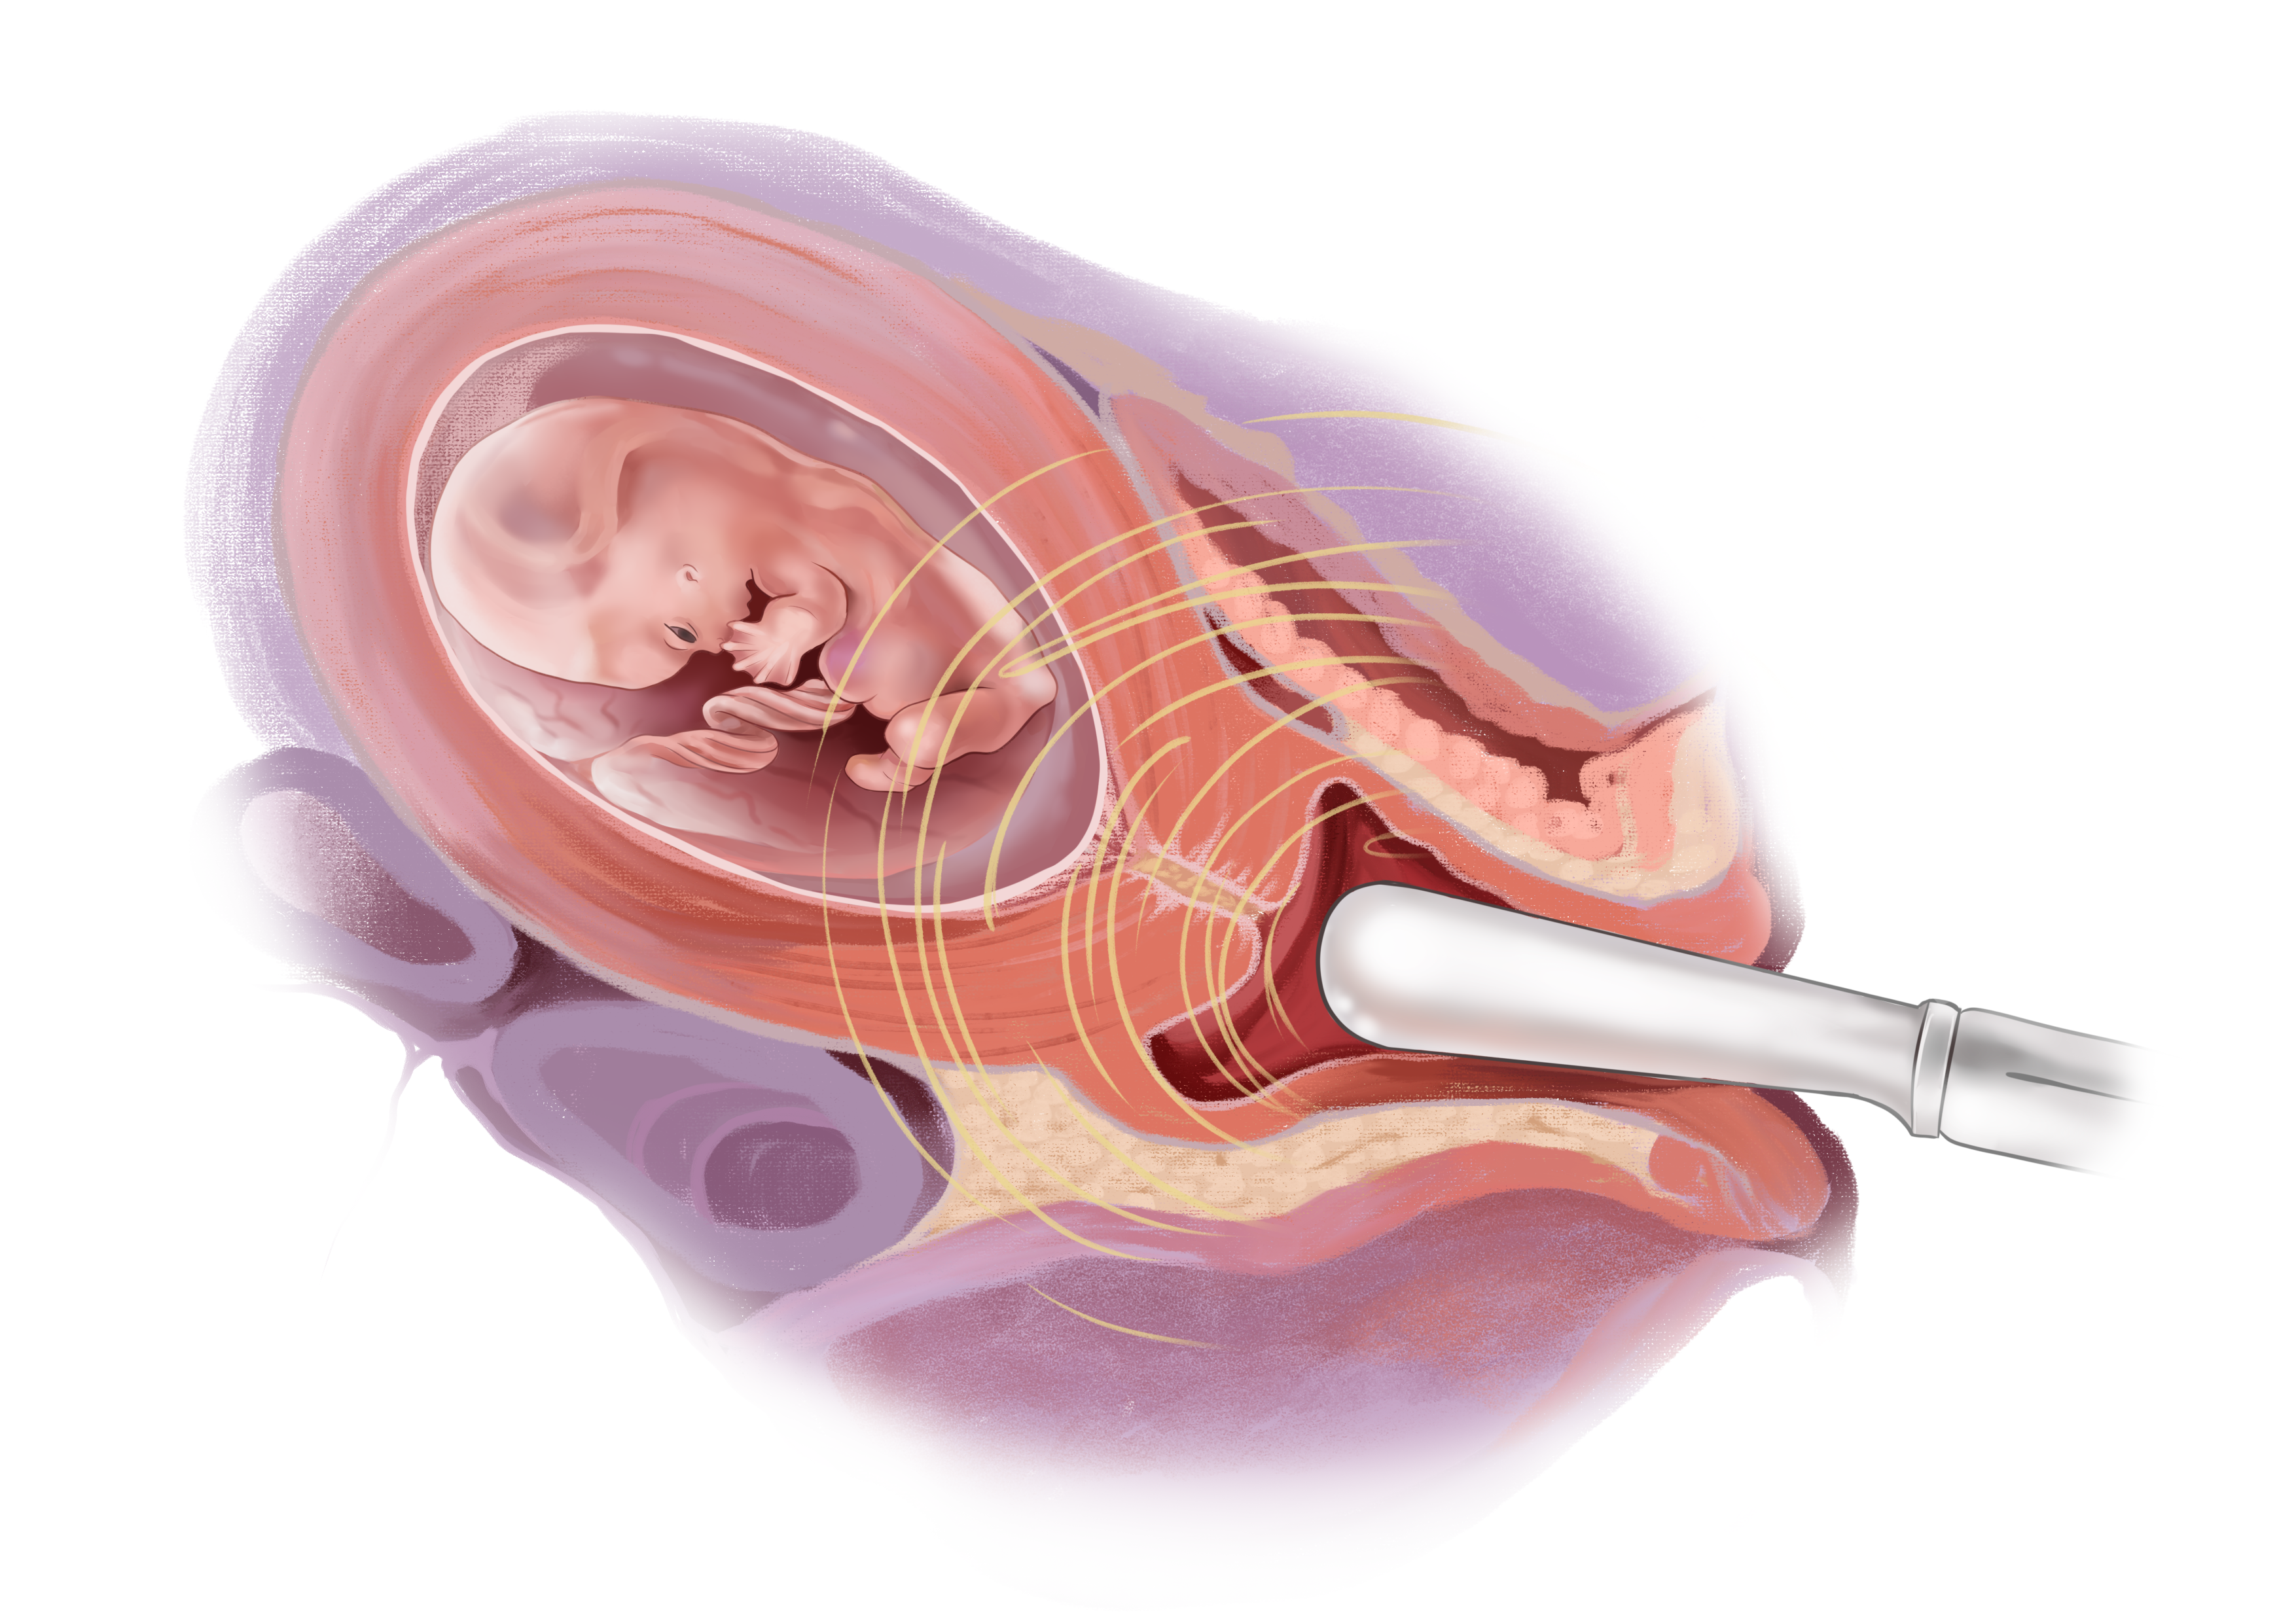

Медицинские аспекты мекония в околоплодных водах